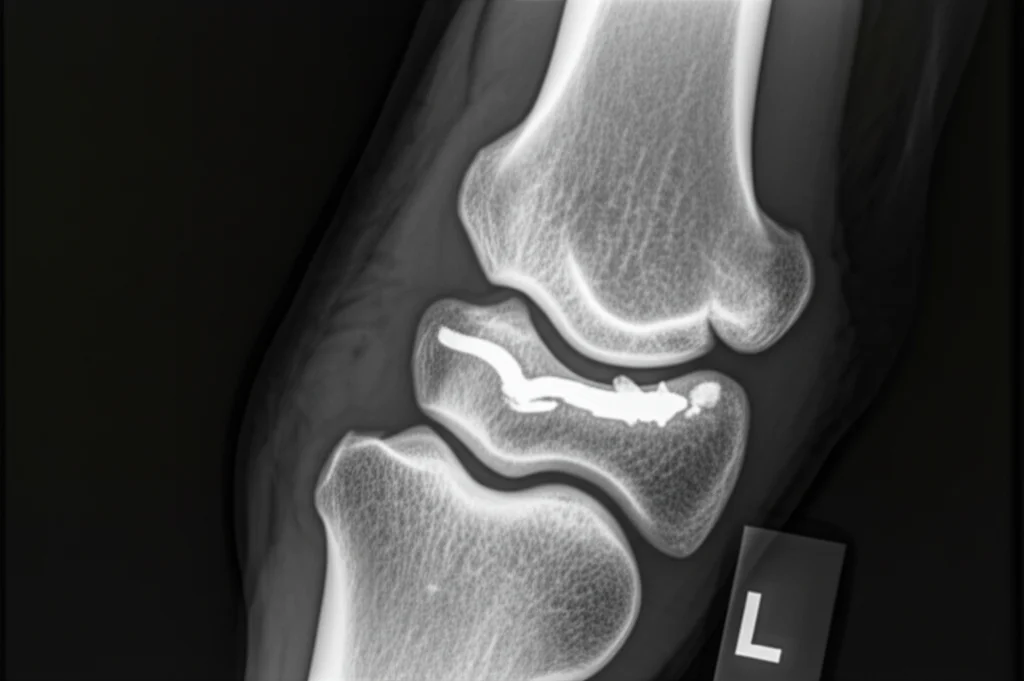

Qui entra in gioco la tecnologia. Per trovare la configurazione ottimale delle viti (quante metterne? a che angolazione?), abbiamo usato la modellazione biomeccanica. Abbiamo iniziato acquisendo immagini dettagliate dell’arto di un cavallo tramite TAC (Tomografia Assiale Computerizzata). Poi, abbiamo prelevato campioni di osso corticale (la parte esterna, dura) e trabecolare (la parte interna, spugnosa) dall’MC III e li abbiamo sottoposti a test di compressione e rilassamento in laboratorio. Questo ci ha permesso di capire esattamente come si comportano questi tessuti sotto carico, definendo le loro proprietà viscoelastiche (in pratica, come rispondono elasticamente ma anche come dissipano energia nel tempo).

Con tutti questi dati, abbiamo costruito un modello matematico e numerico super dettagliato al computer. Abbiamo creato una versione virtuale dell’osso MC III, del fissatore e delle viti. A questo punto, abbiamo simulato l’applicazione di una forza (pari a quella che il cavallo eserciterebbe stando in piedi) e testato ben nove diverse configurazioni di viti, variando il numero (da 4 a 5 viti totali) e l’angolazione rispetto al piano orizzontale (0°, 7° e 14°).